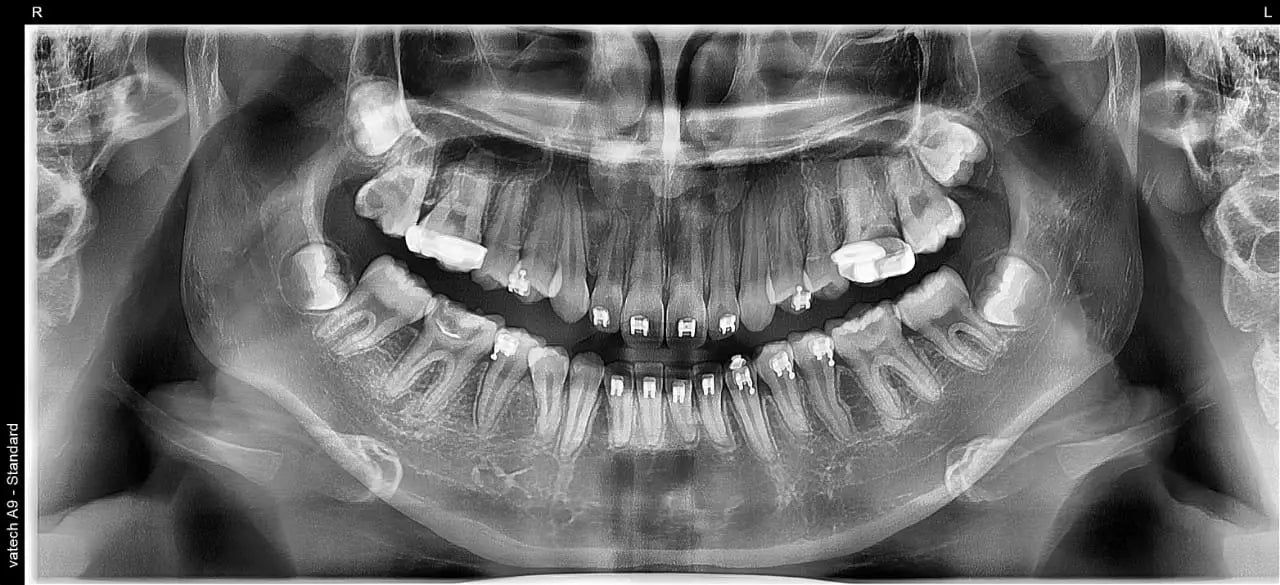

Radiografía panorámica

La radiografía panorámica es una prueba radiológica que sirve para recrear las estructuras óseas de la cara del paciente. De esta manera, el odontólogo obtiene una muestra en dos dimensiones del hueso maxilar superior, la mandíbula y los dientes. Y, por consiguiente, puede determinar el estado de salud de aquellos aspectos que no es posible advertir en su habitual exploración visual.